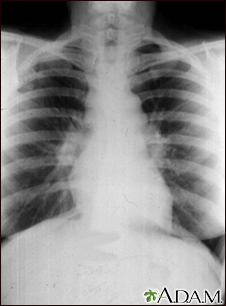

Sarcoid, stage I - chest x-rayBackSarcoid, stage I - chest x-raySarcoid is primarily a lung (pulmonary) disease. In the early stages, a chest film may show enlargement of lymph nodes in the center of the chest near the heart (mediastinum). E-mail FormEmail ResultsName:Email address:Recipients Name:Recipients address:Message: